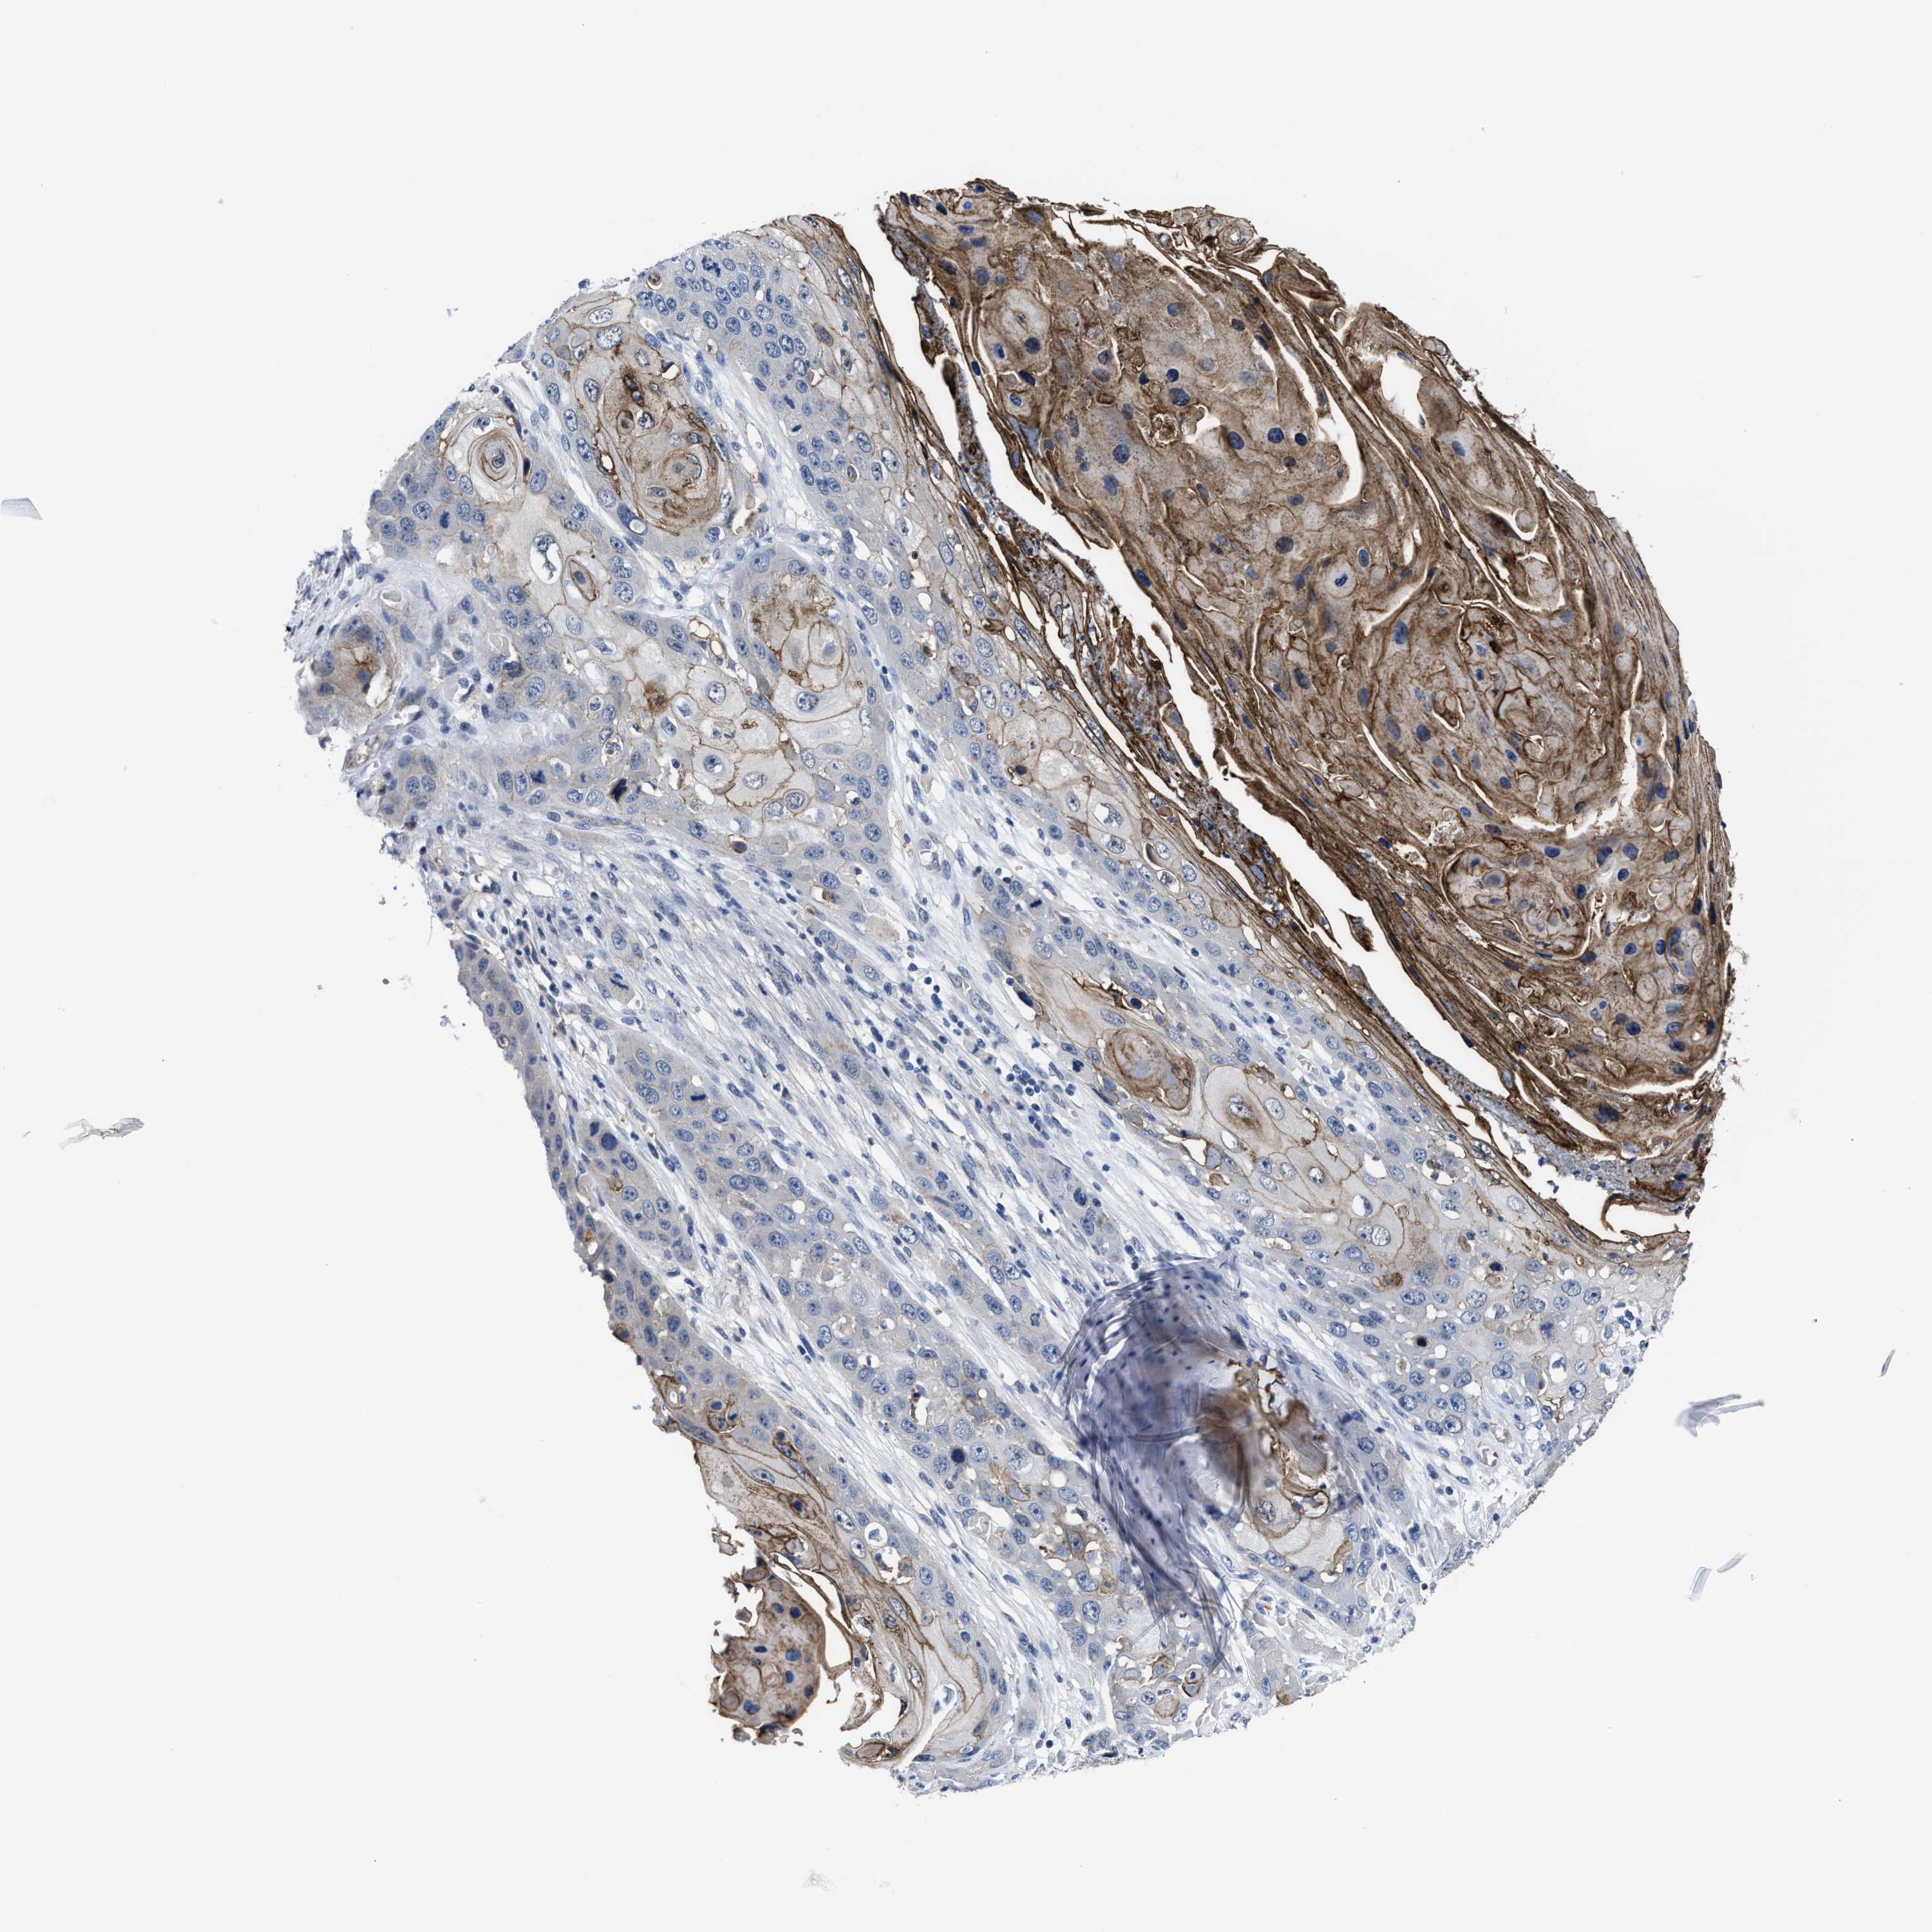

SKIN CANCER - Protein expressioni

A mouse-over function shows sample information and annotation data. Click on an image to view it in a full screen mode. Samples can be filtered based on level of antibody staining by selecting one or several of the following categories: high, medium, low and not detected. The assay and annotation is described here.

Antibody stainingi

Antibody staining in the annotated cell types in the current human tissue is reported as not detected, low, medium, or high, based on conventional immunohistochemistry profiling in selected tissues. This score is based on the combination of the staining intensity and fraction of stained cells.

Each image is clickable and will lead to virtual microscopy that enables deeper exploration of all samples and also displays staining intensity scores, fraction scores and subcellular localization as well as patient and tissue information for each sample.

Antibody HPA061664

Basal cell carcinoma

Squamous cell carcinoma, NOS

Squamous cell carcinoma, metastatic, NOS

BCC, high aggressive